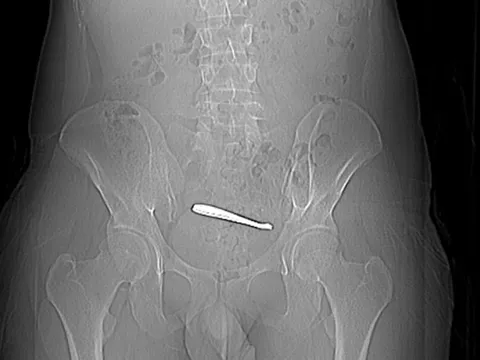

Qua thăm khám và chụp cắt lớp vi tính sọ não, các bác sĩ xác định người bệnh bị đột quỵ xuất huyết não bán cầu phải trên nền tăng huyết áp chưa được phát hiện trước đó. Đây là tình trạng nặng, đe dọa tính mạng.

"Các bác sĩ đã khẩn trương tiến hành phẫu thuật cấp cứu. Ca mổ được thực hiện dưới kính hiển vi phẫu thuật, giúp lấy bỏ khối máu tụ trong não. Sau phẫu thuật, bệnh nhân qua cơn nguy kịch và được giữ lại tính mạng", bác sĩ Nguyễn Lê Duy, khoa Ngoại Thần kinh chia sẻ với Tri Thức.